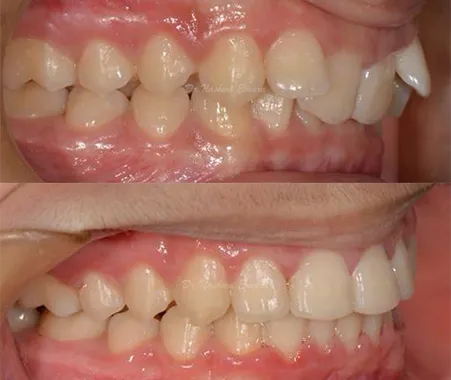

Orthodontics